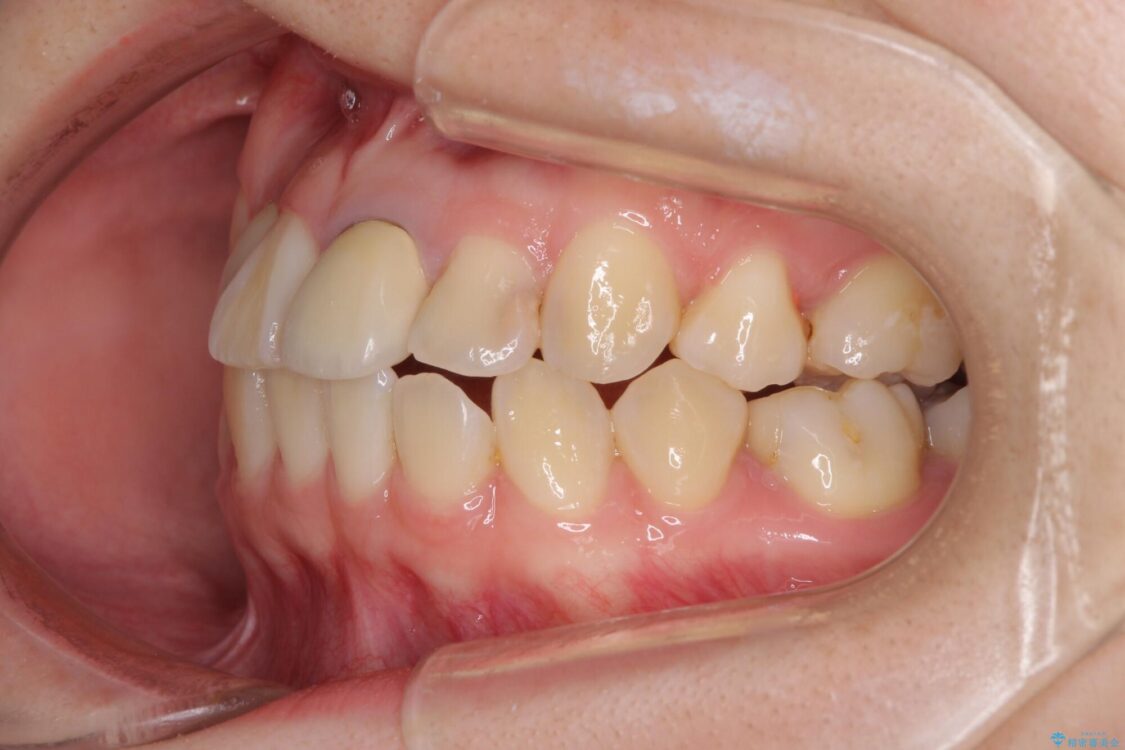

治療前

• 虫歯治療ついでに歯並びの後戻りを改善 インビザラインによる矯正治療 治療前画像